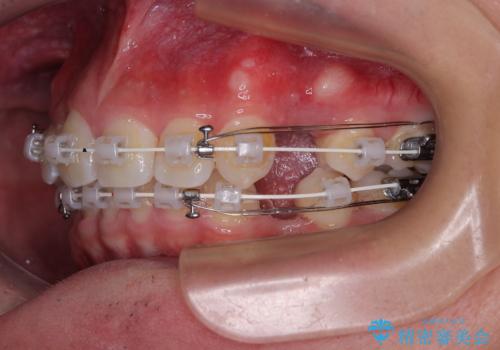

上下左右の第一小臼歯を抜歯してスペースを確保する計画を立てました。

矯正装置には白いプラスチックブラケットと白いコーティングワイヤーを使用し、見た目にも配慮した治療を行いました。